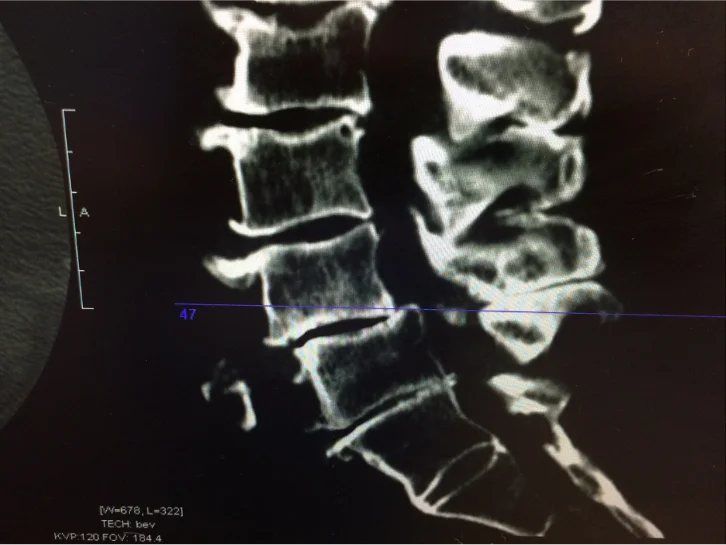

- CT Scan – Provides high-resolution imaging of bones and spinal structures to detect fractures, stenosis, or deformities.